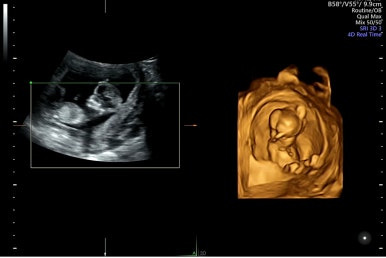

12주 1일

입체초음파 등으로 기형아를 검사하는 시기이다.

입체초음파를 처음 봤는데, 벌써 아기 형태가 많이 생긴 것 같아 너무 신기하고 반한 때이다!

임신 확인 후 보통 2주 마다 검진을 받으러 왔는데 12주는 임신 초기를 지나는 시기로,

특이사항이 없다면 이후에는 4주 이후 검진을 받으러 간다.